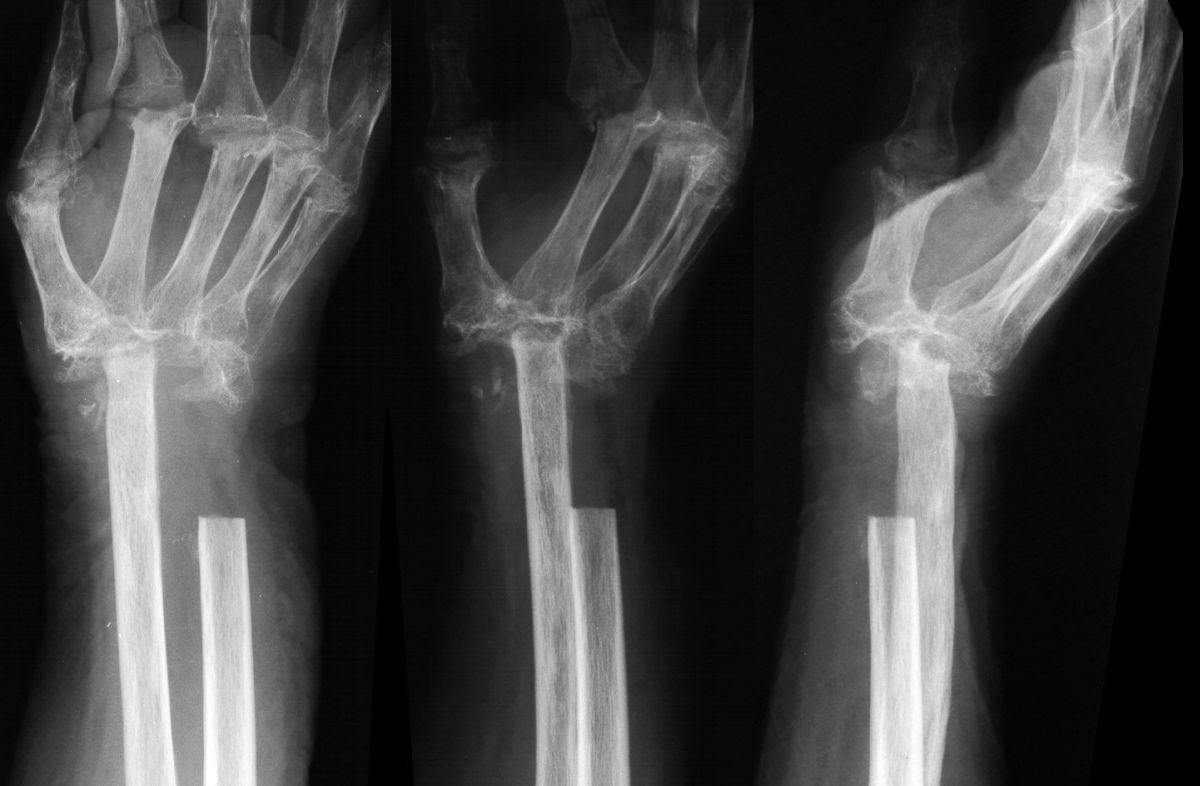

She was treated with radical resection of the infected bone. Intraoperative cultures grew out normal skin flora and she received 6 weeks of appropriate intravenous antibiotics.

Highslide